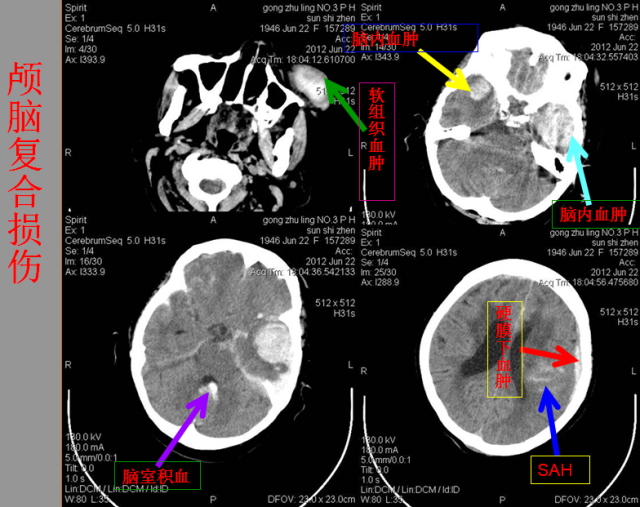

急性颅脑损伤篇

急胸症篇